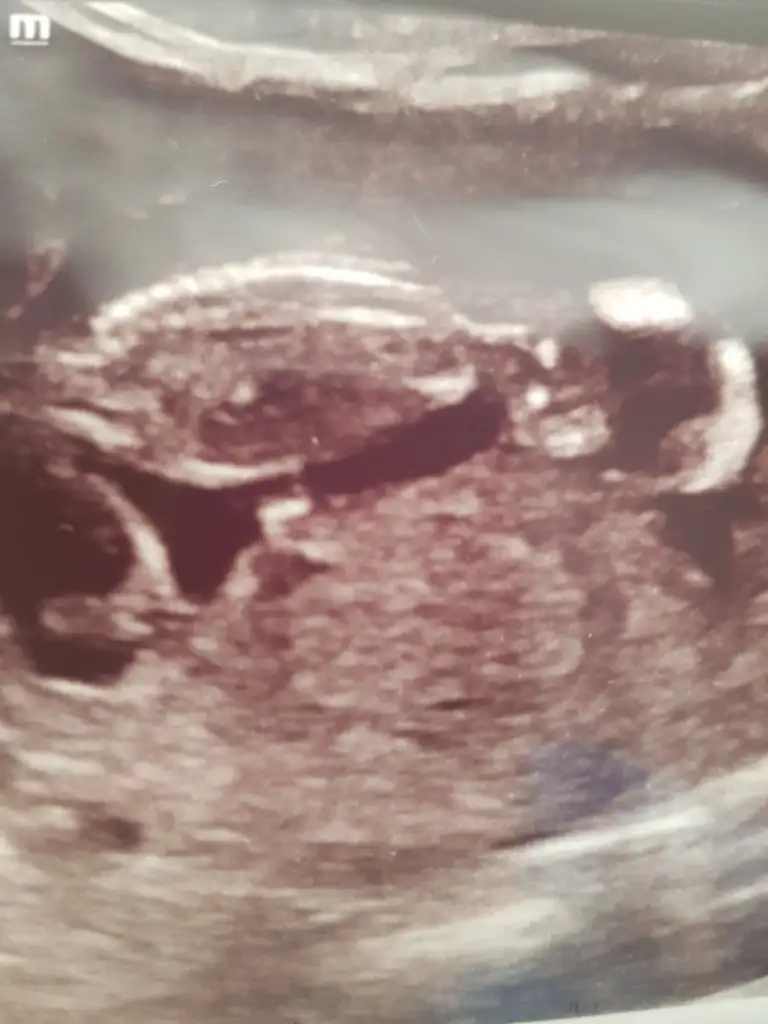

Doktor erkek dedi ama 12.hafta olunca ben emin olamadım. Pipi fotosu da vermiş, ona da bakınca çok emin olamıyorum. Belli bir aya dek benzer gittiği için genital organlar, belki yanılmıştır diyorum..kız istediğim için..umarım bir ay sonra, yanılmışım, kızmış der doktor..